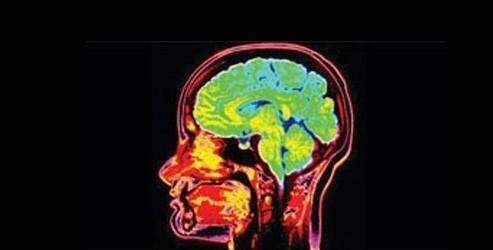

Epilepsi tanısı için uygulanan bazı tetkikler bulunuyor. Epilepsinin temelini oluşturan elektroensefalografi (EEG) ile beyindeki geniş bir sinir hücresindeki dalgalanmalar izleniyor. Beynin yapısıyla ilgili en iyi bilgiyi veren manyetik rezonans görüntüleme (MRG), bir başka tetkik yöntemi olarak kullanılıyor.